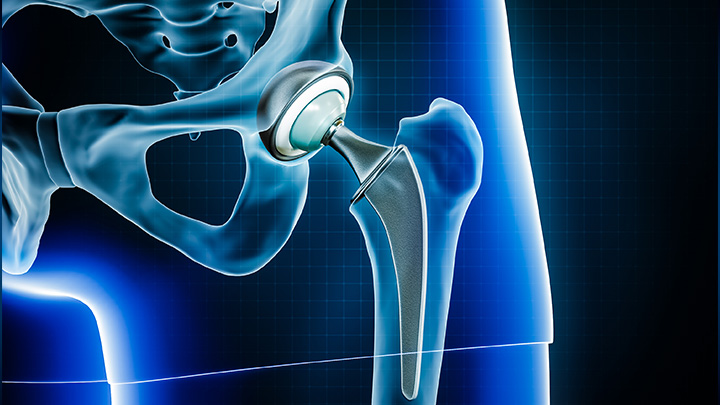

A individualização do cuidado é etapa fundamental do planejamento pré-operatório. No Hospital Moriah, as artroplastias de quadril podem contar com o My Hip Planner®, um sistema que utiliza projeções em 3D para garantir que a prótese seja ajustada e posicionada conforme a anatomia de cada paciente.

Este planejamento detalhado auxilia o cirurgião na execução de uma cirurgia mais precisa, antecipando e evitando possíveis complicações intraoperatórias, como desigualdade de comprimento da perna, instabilidade ou detecção de riscos e falhas no implante.

Um sistema de navegação com tecnologia digital que auxilia os cirurgiões a realizarem com exatidão e precisão a cirurgia de substituição do quadril. Considerada não invasiva, a tecnologia permite que o cirurgião verifique, durante o procedimento, o posicionamento correto para a prótese, reduzindo a probabilidade de deslocamento do quadril e aumentando a estabilidade da articulação.